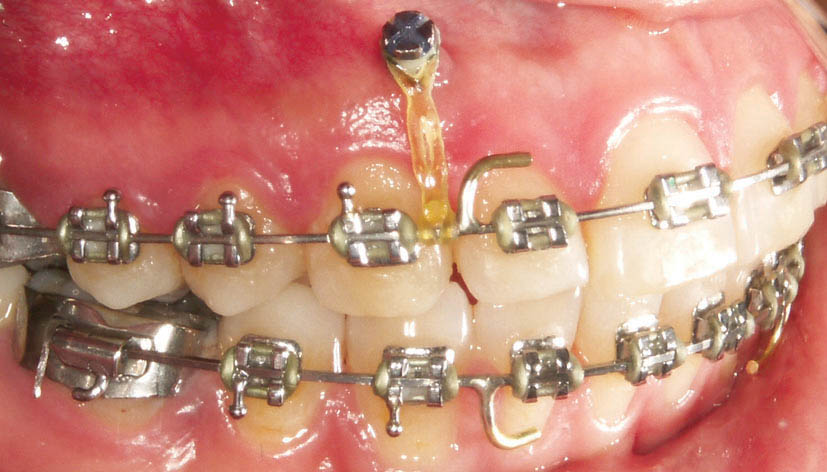

شکل 222-1: در بیمار gummy smile که دیپ بایت هم باشد مینی اسکرو در ناحیه لثه چسبنده بالای ریشه سانترالها میگذاریم تا سگمنت قدامی اینترود شود.